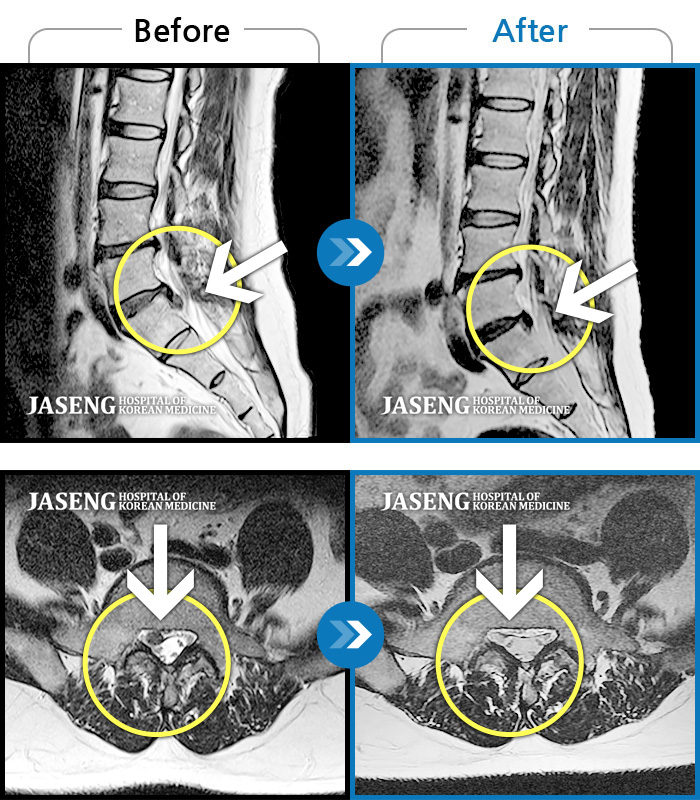

허리디스크

일산 · 배영현 교육수련부장

허리, 좌측 골반부터 좌측 다리로 통증 및 저림이 지속되고 좌측 다리의 감각이 둔함

촬영시기

2024.09.30 ~ 2025.11.25

2025.12.05